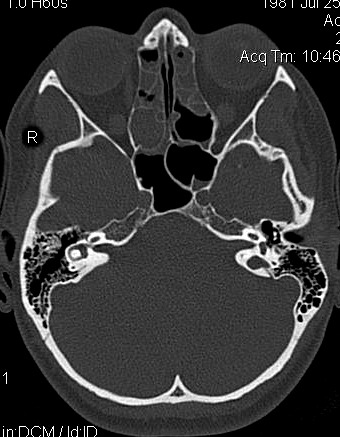

TC exostosis occipital congénica.

TC exostosis occipital congénita.

JFC Aticitis colesteatomatosa.

JFC Colesteatoma dehiscente.